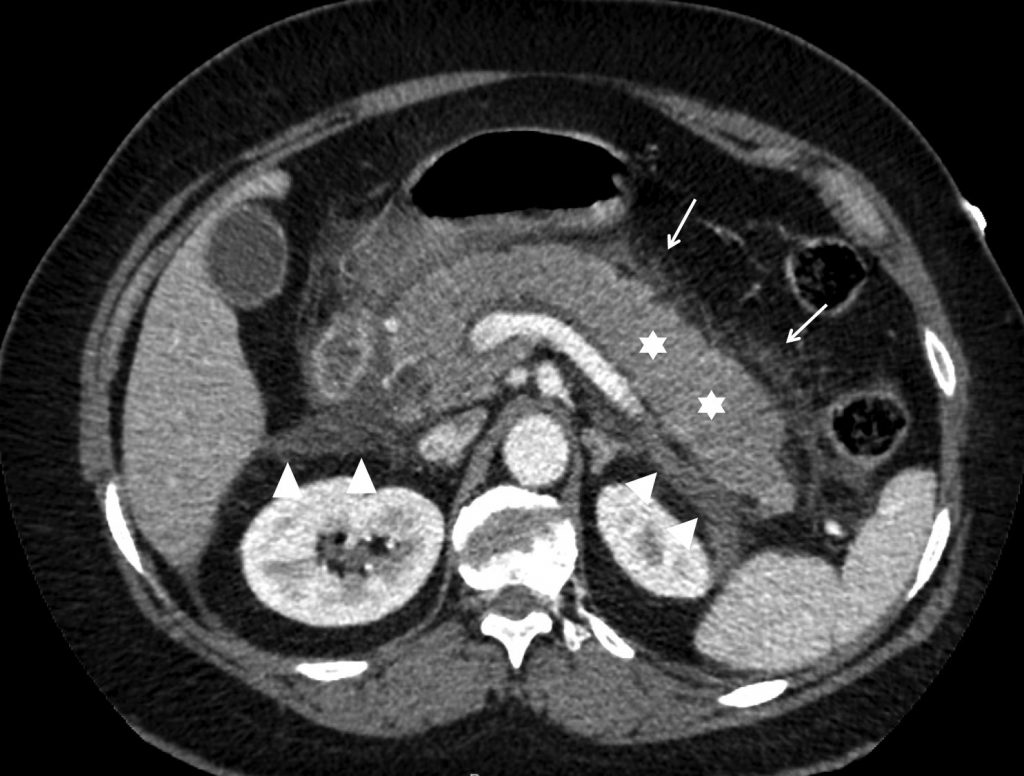

Fig. 11.1. Patiente de 46 ans adressée pour douleur épigastrique aiguë.

La biologie permet de diagnostiquer une pancréatite aiguë. Coupe scanner avec injection de produit de contraste iodé montrant un rehaussement normal et complet de la glande pancréatique (nécrose à 0 %, 0 point), un œdème de la glande pancréatique prédominant en région corporéo-caudale (étoiles blanches), une infiltration de la graisse péripancréatique (flèches blanches) et des collections aiguës liquidiennes le long des fascias pararénaux antérieurs (têtes de flèches) (4 points). Pancréatite aiguë interstitielle sévère (CTSI à 4).

Source : CERF, CNEBMN, 2022.